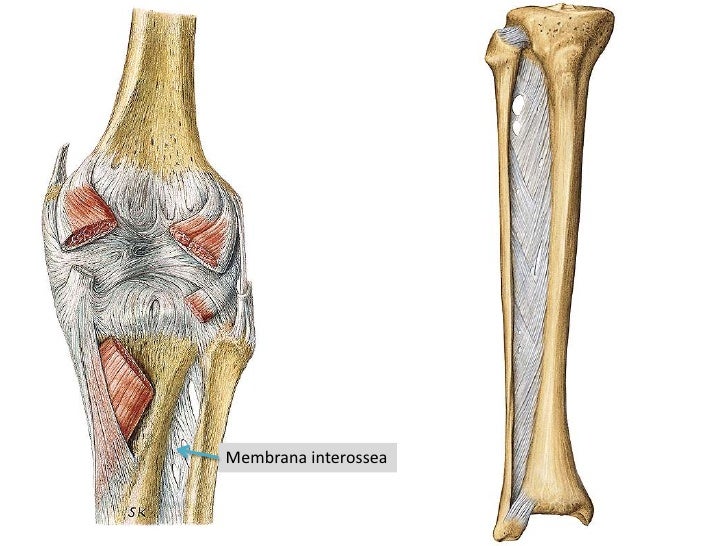

Структура и анатомия синдесмоза: научные иллюстрации